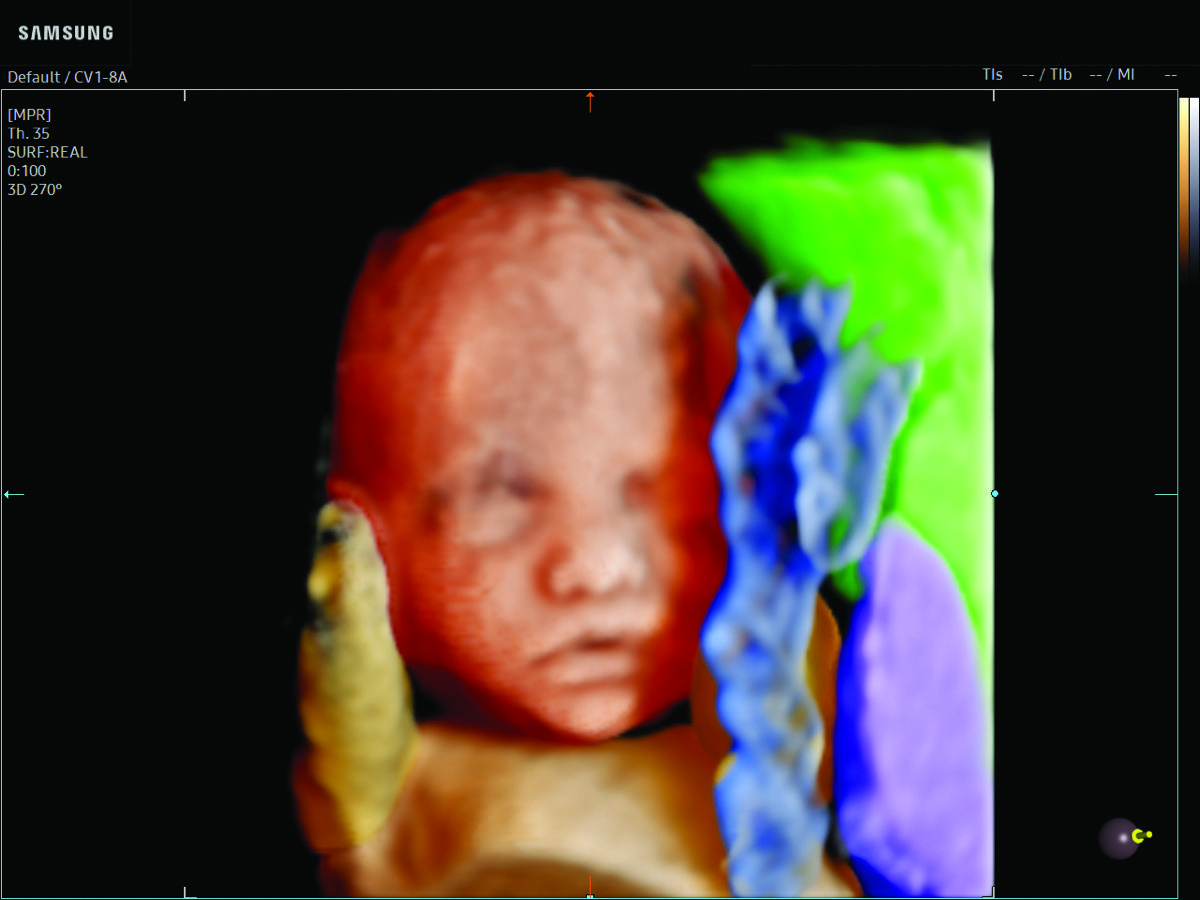

Comprehensive, advanced and expert MFM care for high-risk pregnancies

- Fetal anomalies